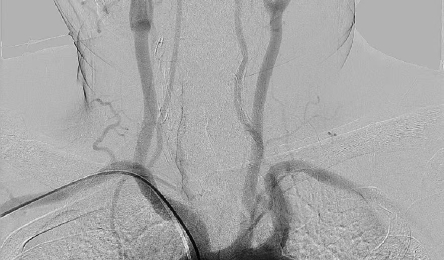

• 介入新時代 | 我院開展首例經桡動脈全腦血管造影(yǐng)術(shù)

近日(rì) 我院成功開展首例 經桡動脈全腦血管造影(yǐng)術(shù) 得(de)到了患者及家屬好評 患者情況 王某,男,52歲,因“發作(zuò)性頭暈、耳鳴1年(nián),加重1天”爲主訴入院。MRA(磁共振血管)提示:左側鎖骨下動脈起始段...